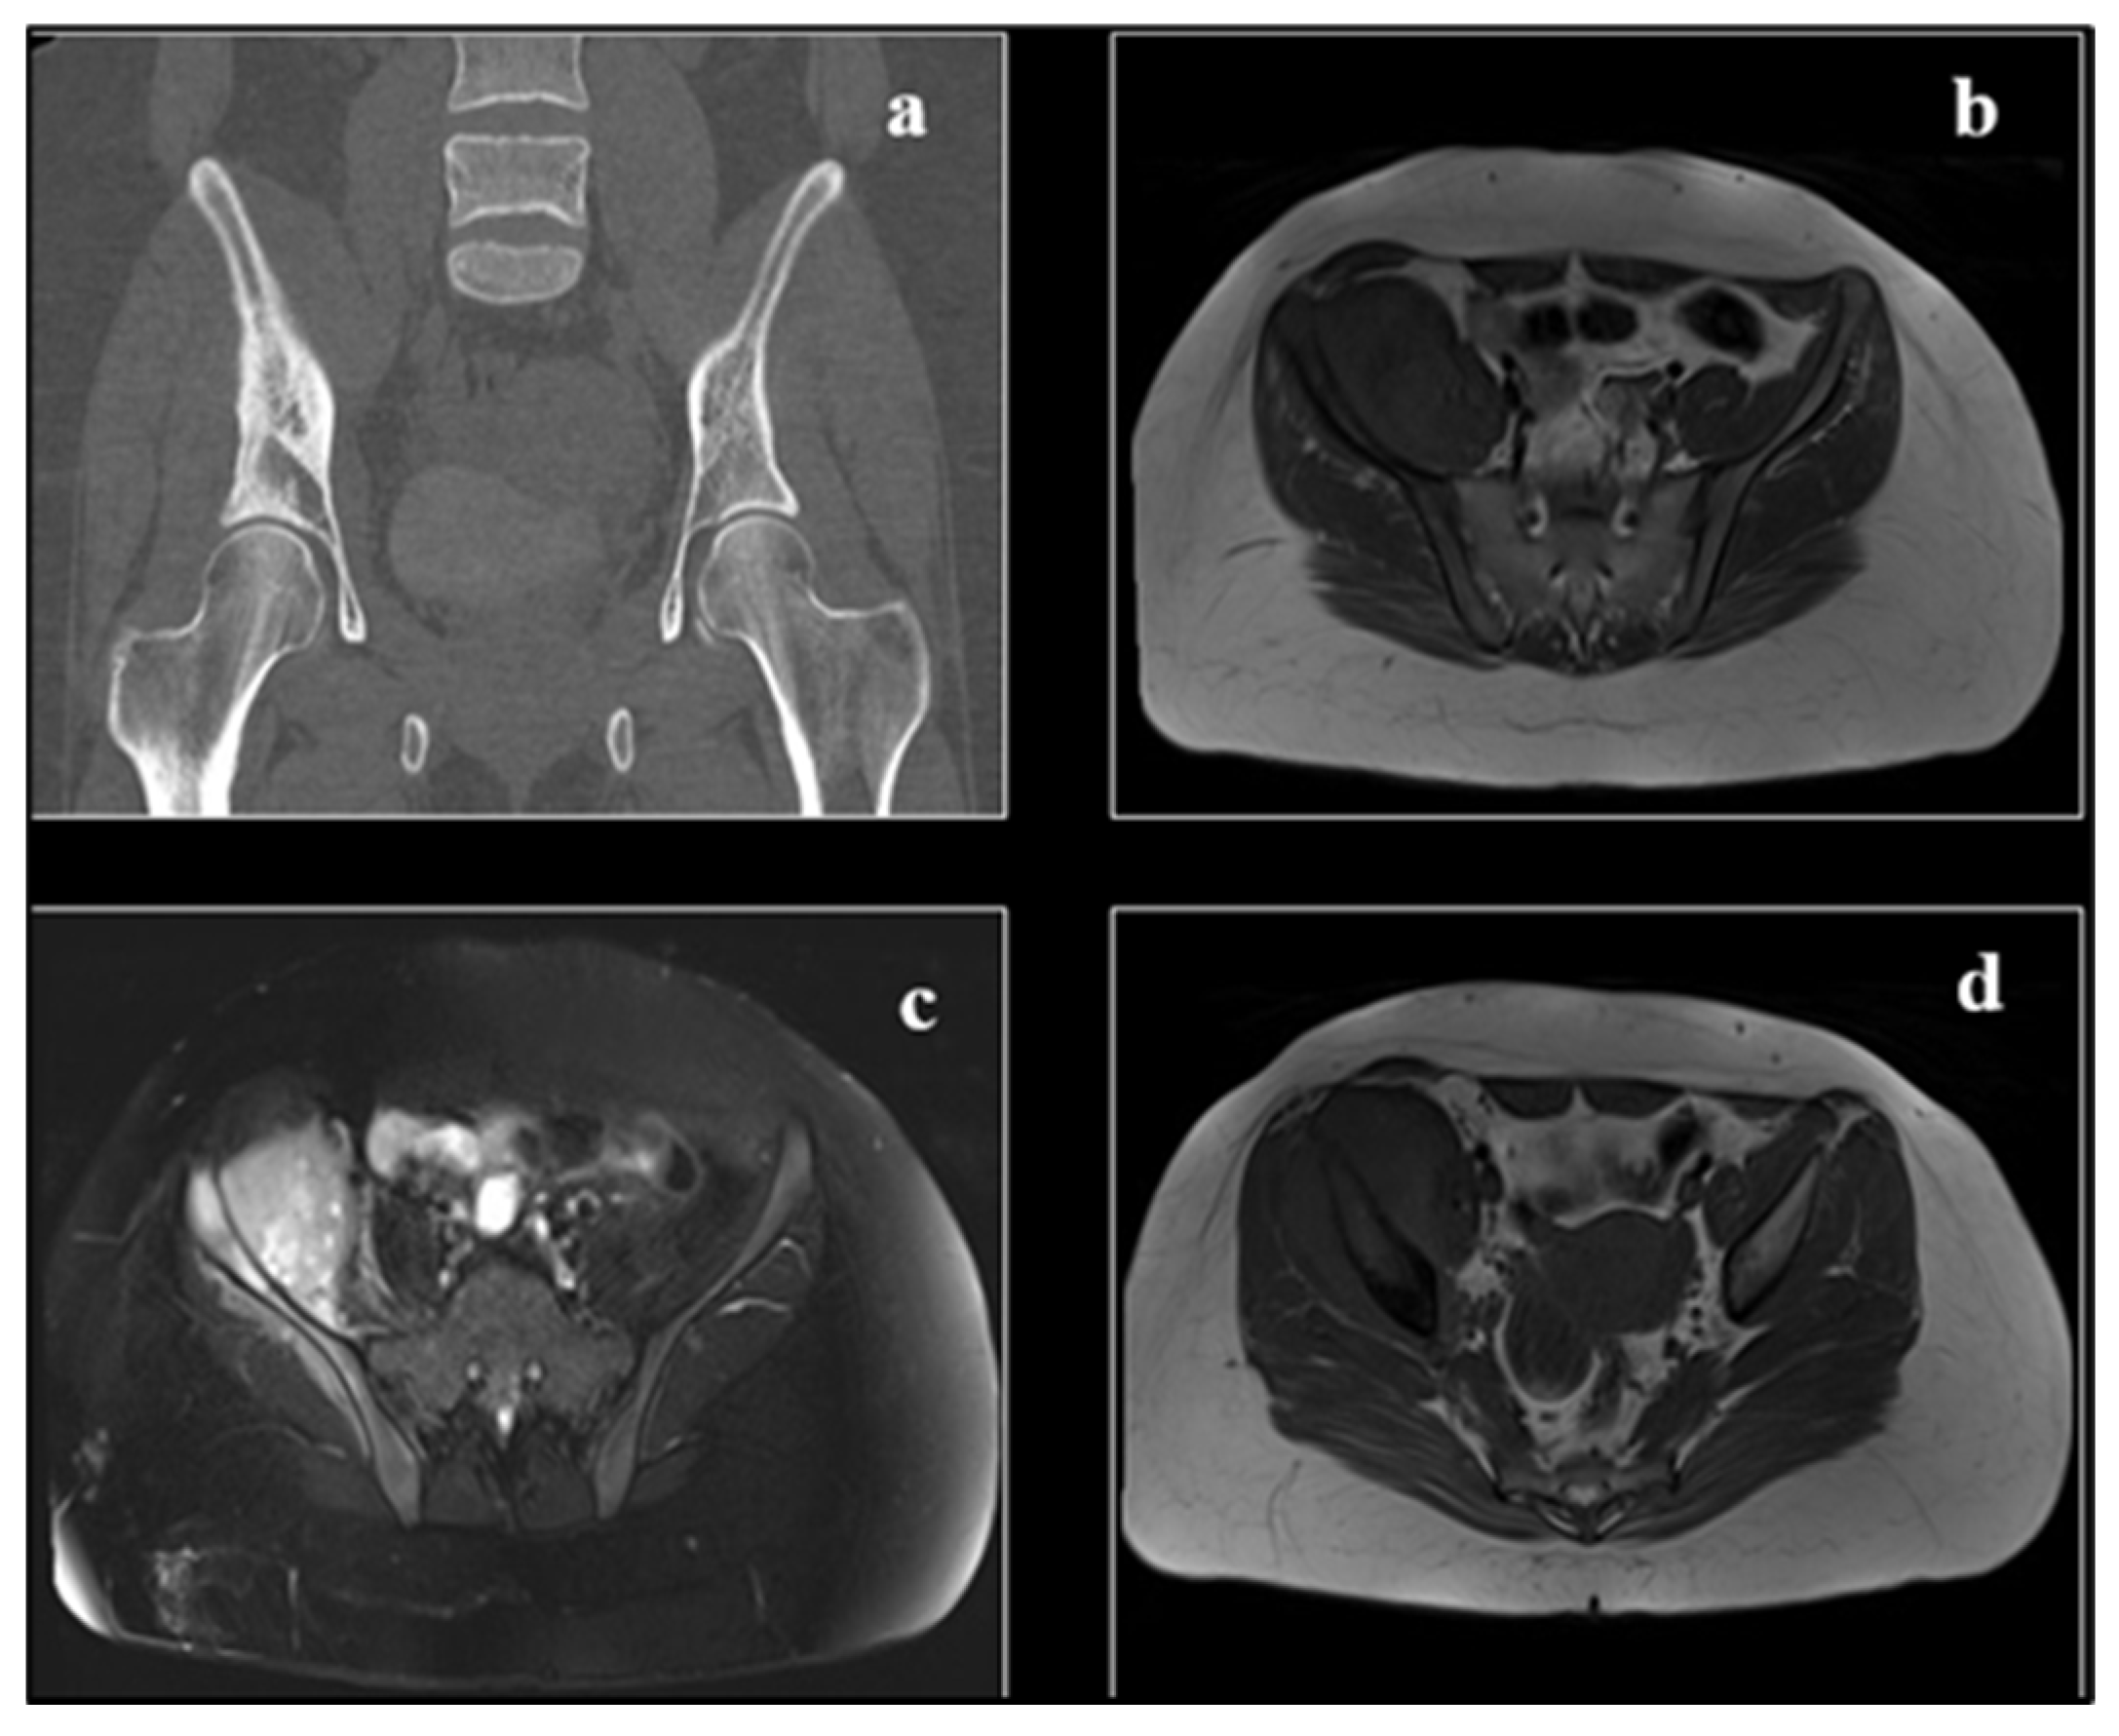

The medullary canal is often involved (Figure 2). The growth of cartilage or physis can hinder its spread to the epiphysis.

CT allows the evaluation of the cortical integrity (small osteolytic areas of compact) and alterations of the cancellous trabecular meshwork, but above all, it demonstrates fine tumour calcifications (Figure 2).

Figure 2. The structural features of the lesion and its encroachment into the paraosteal soft parts are well documented by CT scan (a). MRI (b) in sagittal section in T2-weighted sequence, showing the occupation of the medullary canal (with clear delimitation in correspondence of the growth cartilage) by the lesion, which emits a low-intensity signal where the osteosclerotic component prevails and high-intensity signal where the osteolytic component prevails. The ‘sleeve-like’ encroachment into the soft parts is evident. Radiopaedia.org.

Figure 7. (a) CT image demonstrating cortical destruction, medullary extension, and periosteal reaction of an osteolytic aggressive lesion involving the right iliac bone. Large soft tissue mass that is connected to the right iliacus muscle. (c) T2 bright heterogeneous signal with heterogeneous post-contrast enhancement (d); (b) T1 iso to low signal. Along with the infiltration of the iliacus muscle and, to a lesser extent, the gluteus minimus muscle, the associated soft tissue component is observed penetrating and degrading the iliac bone. Radiopaedia.org.